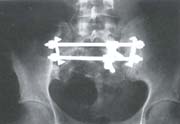

Con respecto a los abordajes, el posterior fue el más utilizado: Percutáneo 8 pacientes (36,4%); abierto transglúteo, 7 pacientes (31,8%); abierto por línea media sacra, 3 pacientes (13.6%). Por vía anterior se abordaron 4 pacientes (18,2%), (figura 5). El método de fijación más frecuentemente empleado fueron los tornillos iliosacros, 10 pacientes (45.4%); seguido de barras iliosacras con tornillos sacros, 4 pacientes (18.2%) y fijación anterior con placas, 3 pacientes (13.6%); barras sacras con tornillos iliosacros, 2 pacientes (9.1%) (figura 6).

Fig. 4D Radiografía postoperatorio donde se aprecia la fijación con tornillos iliosacros y placas en la sín

El componente anterior de la pelvis, requirió estabilización quirúrgica en 14 pacientes (70%); 8 pacientes (57%) con fijador externo, y 6 pacientes (42%) con placas en la sínfisis púbica.